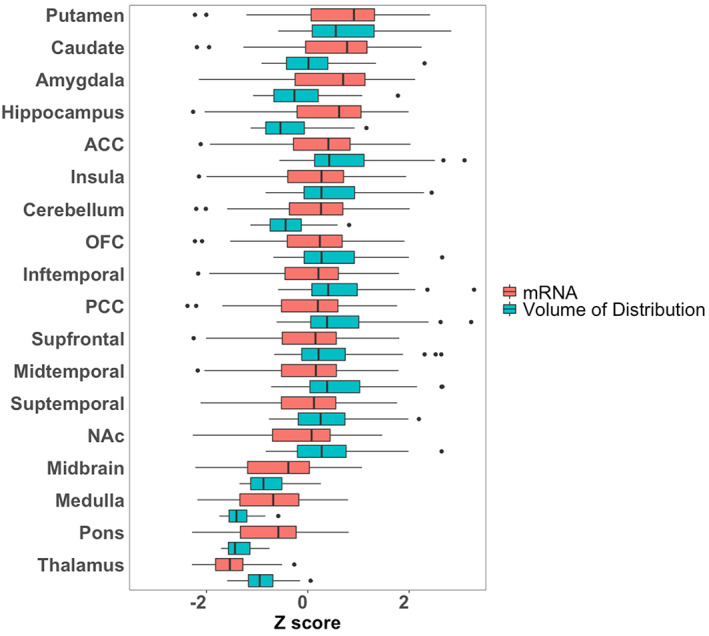

Mean distribution of F18‐FMPEP‐d2 PET scans from 36 subjects is visualized in Figure 1. The distribution of CNR1 mRNA expression and V T of F18‐FMPEP‐d2 PET from each ROI is shown in Figure 2. Strong auto‐correlation was observed both for V T from F18‐FMPEP‐d2 PET scans (inter‐subject: mean correlation coefficient rho: .8674) and for CNR1 mRNA expression from the Allen Human Brain Atlas (inter‐probe: mean correlation coefficient rho = .9148), which ensures consistency of observations. Between V T of F18‐FMPEP‐d2 PET scans and CNR1 mRNA expression from 18 ROIs, moderate strength of correlation was observed (rho = .5067, p = .0337). The correlation between V T of F18‐FMPEP‐d2 PET scans and mRNA was significant in subcortical regions (rho = .8182, p = .0068), not in cortical regions (rho = .5952, p = .1323). Strong positive correlation was also found between CNR1 mRNA expression and H3‐CP55940 binding from 11 ROIs (r = .6336, p = .0364), which validates the finding between F18‐FMPEP‐d2 PET scans and CNR1 mRNA (Figure 3). The correlation between V T of F18‐FMPEP‐d2 PET scans and H3‐CP55940 binding from 15 ROIs was not significant (r = .5025, p = .0563). The slope estimates (slope = 4.3192; p < .0001) of the regression were used to transform F18‐FMPEP‐d2 PET atlas into density map atlas (Figure 4, https://neurovault.org/images/782713/).

The use of cannabinoids is of growing interest since several studies supported a great variety of pharmacological properties that would be useful in different pathologies, including neurological and psychiatric disorders (Black et al., ref. 2019). THC derivatives dronabinol and nabilone are the first cannabinoids approved by FDA for the treatment of acquired immunodeficiency syndrome‐induced anorexia (dronabinol) and chemotherapy‐induced nausea and vomiting (dronabinol and nabilone) in 1985 (Khalsa et al., ref. 2022). Also, CBD was approved in 2018 for treating seizures associated with Lennox–Gastaut syndrome or Dravet syndrome (Khalsa et al., ref. 2022). An additional cannabis‐based drug is nabiximols, a combination of THC and CBD, which was approved for the treatment of spasticity in multiple sclerosis (Khalsa et al., ref. 2022). CB1 receptor is a key component of the endocannabinoid system, which consists of cannabinoid receptors, endogenous ligands, and their metabolic enzymes (Tao et al., ref. 2020). CB1 receptor, encoded by CNR1 gene, is expressed in cortex, hippocampus, amygdala, basal ganglia, substantia nigra, and cerebellum (Gifford et al., ref. 2002; Herkenham et al., ref. 1990; Mackie, ref. 2005; Westlake et al., ref. 1994) (Figures 1 and 2), and these circuits may be responsible for the behavioral effects of cannabis (Mackie, ref. 2005). CB1 receptors are found primarily in the presynapses of the neurons, unlike other receptors of neurotransmitters which are located in the postsynapses (Mechoulam & Parker, ref. 2013). Activation of CB1 receptors leads to a decrease in cyclic adenosine monophosphate accumulation (cAMP), inhibition of cAMP‐dependent protein kinase, and stimulation of mitogen‐activated protein kinase activity. CB1 receptor level is increased from adolescence to adulthood in rats, showing its importance in neurogenesis (Aguado et al., ref. 2006; Verdurand et al., ref. 2011). Also, alterations of CB1 receptor availability have been reported in neuropsychiatry disorders, such as post‐traumatic stress disorder and schizophrenia (Neumeister et al., ref. 2013; Ranganathan et al., ref. 2016; Volk et al., ref. 2014). Therefore, CB1 receptor has become a target for drug development and in vivo imaging biomarker for neuropsychiatric disorders (Van Laere, ref. 2007).